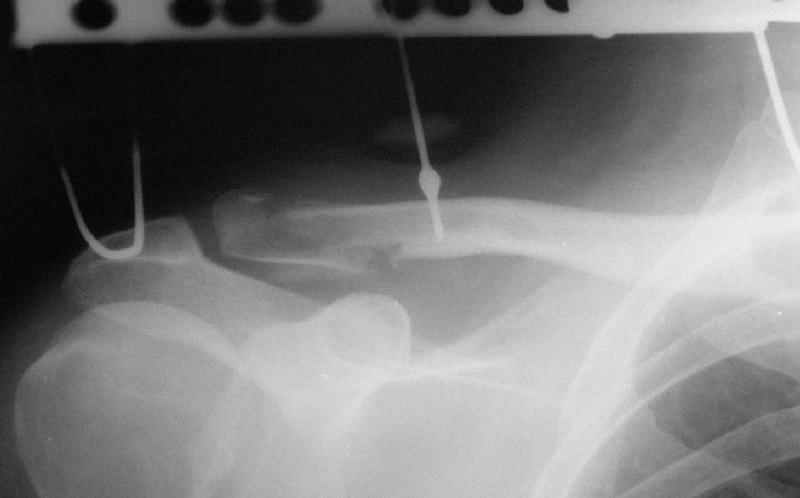

При данных повреждениях возможно применение как АВФ, так и открытые способы лечения. Выбор в основном определяется давностью травмы, требованиями больного и отношением хирурга к тому-или иному способу лечения. В данном случае, учитывая смещение фрагмента с прикреплением кл-кл связки каудально, необходимо было "утопить" проксимальный отломок, что и сделано АВФ.

АПК> молодому пациенту по поводу оскольчатого перелома акромиального конца

АПК> ключицы

АПК> После перелома "толкателя"

"Толкатель" - укороченная спица с упором. На первичных снимках - оскольчатый перелом, отдельный фрагмент с местом прикрепления кл-кл связки сместился каудально.

Действительно, на представленном вами первично снимке есть кусок спицы... Но что должно было произойти с больным (или что-то иное?), чтобы спица-толкатель сломалась ниже расположенного на ней упора? Оправдано ли использование таких спиц? Или аппарата?

Больной хоть и молодой но отнюдь не ребенок (судя по снимкам)... Почему было не использовать стержень-толкатель, если уж принято было решение за первичный ЧКОС?